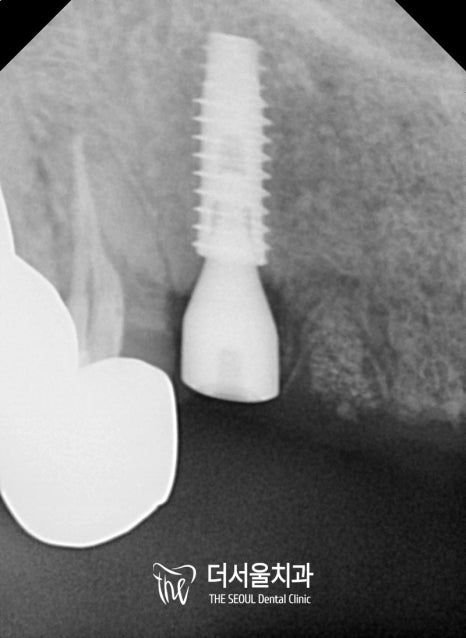

그런데 오늘 집중적으로 보여드릴 곳은

윗니 2개인데요.

앞니 깨짐, 부러짐이 나타나

발치 후 임플란트 수술 및 브릿지로

연결시켜 사용할 수 있도록 해드려야 되었는데요.

오랜 기간 치아가 없는지 되셨는지

뼈가 어느 정도 소실된 것을 볼 수 있었습니다.

정밀검사를 진행해봐야 알겠지만,

뼈이식을 해야될 가능성을 배제할 수 없었죠.

폭이나 두께, 비구개신경을

체크하여 픽스처를 심을 때,

위치 선정을 잘 해드려야 되었습니다.

아무래도 앞니는 다른 어떤 부위들보다

뼈 두께가 얇고 깊이 또한 얕기 때문에

식립에 있어 어려움이 많을 수밖에 없습니다.